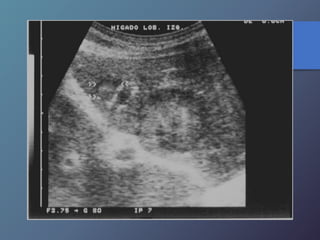

Neoplasias Hepáticas Malignas

Carcinoma Hepatocelular

• Antecedente de hígado cirrótico

• Relación 5:1

• Puede aparecer solitario, nódulos

múltiples o infiltración difusa.

• Ecograf. Similar a mt, infiltr. Grasa focal

hemangioma cavernoso

• Invasión a vena porta

• Alfa feto proteína elevada

• Variable desde mas hipoecoicas hasta complejas o

Hiperecogénicas.

• Los chc pequeños son hipoecoicos, con halo periférico

fino que Corresponde a la capsula.

• Los chc de mayor diámetro, tienden a ser Heterogéneas,

complejas.

• Son hipervasculares, con vasos dismórficos.

Características Ecográficas